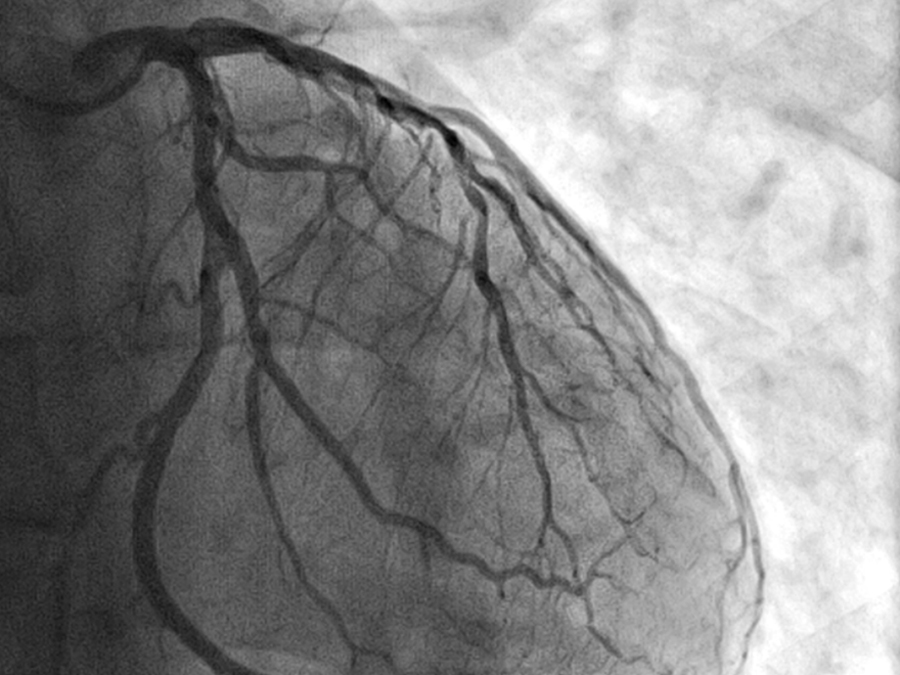

Aufnahme der Blutgefäße auf einem Herzmuskel.

Auf dieser Koronarangiografie ist gut zu erkennen, wie sich die Blutgefäße auf dem Herzmuskel verzweigen. (Bild: kalus/istockphoto)

Die Herzkranzgefäße lassen sich mit einem Straßennetz vergleichen: Arterien und Venen bilden die Hauptverkehrswege, von denen zahllose kleinere und kleinste Verbindungsstraßen und Zufahrtswege abzweigen. Wenn eine dieser kleinen Straßen gesperrt ist, hat das kaum Auswirkungen auf den gesamten Verkehrsfluss. Wenn jedoch genug Abfahrten geschlossen sind, wird der Verkehr auch auf der Hauptstraße dichter. Im schlimmsten Fall kann das zum Kollaps des gesamten Systems führen – einem Herzinfarkt.